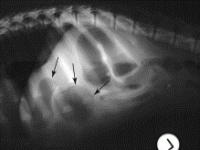

• Abdominal Radiographs

• Diagnostic Imaging